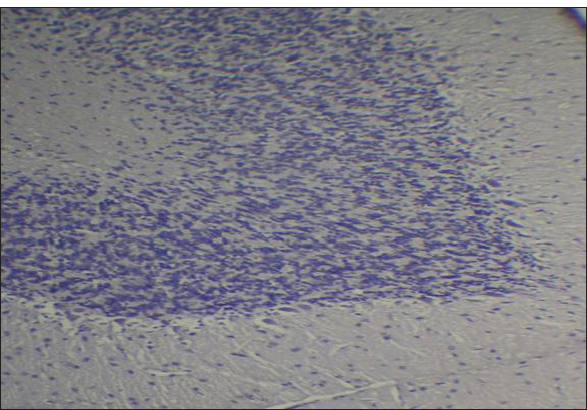

Fig. 2. Effect of gemcitabine, gemcitabine + ALC (25 mg/kg/bw), and gemcitabine + ALC (300 mg/kg/bw) on serum AChE. Histological resultsAccording to the histological investigation, the central nervous system did not contain any beta clusters. The experimental beta-amyloid turns red because it is stained using the pigment Congo red, indicating that the central nervous system is secure from beta-amyloid buildup in the absence of treatment (Fig. 3). The gemcitabine group showed an increase in beta-amyloid accumulation in the rat’s brain, which is stained in red color as shown in Figure 4. However, compared to the gemcitabine group, rats administered gemcitabine plus ALC (25 mg/kg/bw) showed a significant reduction in the buildup of beta-amyloid in the rat’s brain, as depicted in Figure 5. Furthermore, as illustrated in Figure 6, rats treated with gemcitabine + ALC (300 mg/kg/bw) exhibit a significant reduction in the buildup of beta-amyloid in their brains when compared to rats treated with gemcitabine + ALC (25 mg/kg/bw).

Fig. 3. Photomicrograph of the control group’s brain section showing the normal histological architecture without the accumulation of beta-amyloid (congo red, 4×).